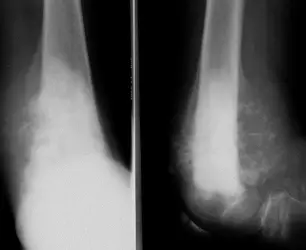

| Compartment Syndrome | Increased pressure within a closed fascial compartment, leading to reduced tissue perfusion, hypoxia, and irreversible muscle and nerve damage. Causes: Fractures (especially tibia/forearm), severe soft tissue trauma, arterial injury, burns, tight casts/dressings, post-ischemic reperfusion swelling, IV fluid extravasation, and bleeding disorders (e.g., hemophilia). High-Risk Notes: Pain may be absent in altered consciousness, children (monitor analgesia response), polytrauma, sedated/epidural cases, or concomitant nerve damage. Open fractures do not always decompress pressure. Gross/Clinical: -tense, shiny leg swelling with blisters in compartment syndrome.Imaging: - Intraoperative fasciotomy | History/Symptoms: Pain out of proportion to the injury (e.g., a “bursting” sensation), which is not relieved by analgesia. Clinical Features (The 5 P’s): - Pain with passive stretch (early, key sign; e.g., ankle dorsiflexion for leg, wrist for forearm). - Paresthesia (early). - Palpable tense swelling (shiny skin, blisters: clear=mild, serosanguinous=severe, bloody=worst; dusky/pallor skin). - Pallor, Paralysis, Pulselessness (late, ominous signs; pulses often palpable until late). Investigations: Primarily a clinical diagnosis (high suspicion key). Compartment pressure measurement can confirm: absolute pressure >30 mmHg or Delta Pressure (Diastolic BP - Compartment P) ≤ 25 mmHg. | Initial: ABCs, supplemental oxygen. Remove all circumferential dressings, casts (bivalve to skin), and splints. Elevate the limb to heart level (not above; higher reduces inflow). Correct any hypotension. Surgical: Urgent Fasciotomy if no response within 1h or confirmed pressure (prophylactic in high-risk like major osteotomy). Release all compartments/skin with long incisions; debride necrotic muscle via 4C’s (early: pink/red, soft, contracts/bleeds on pinch; late: dark, firm, no response); preserve neurovascular. Wound open (bulky dressing/splint, VAC, or boot-lace gradual closure); repeated inspections x48h; coverage in 3-5 days (skin graft usual; flap if nerves/vessels/bone exposed). | Cellulitis, Deep Vein Thrombosis (DVT), Arterial occlusion, Severe soft tissue injury without compartment syndrome; equivocal cases in polytrauma. | Complications: Volkmann’s ischemic contracture (permanent deformity, weakness, sensory loss, chronic pain). Contraindications (Fasciotomy): Confirmed >48h (irreversible damage, high infection risk from dead tissue); crush injuries with already necrotic muscle. |